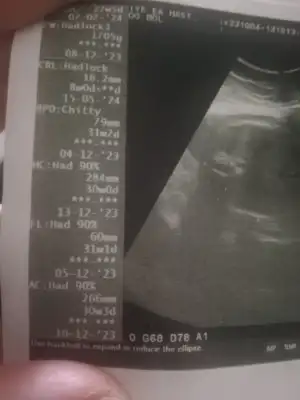

İkizler için çok normal değil mi kiloları. Altta imzanda bile 1780 gr diyor ki biliyorsun farklı ölçümler olabiliyor. Hem belki son zamanlarda daha çok kilo alırlar annesi

Bilmiyorum ki normal diyo dr da perinatolojiye gitsem mi acaba kafam karıştıCanım alttaki açıklamada 1780 gr olmalı diyor. E seninkiler ikiz, kilolarının böyle olması normal değil mi? Sen hiç kötü düşünme, alırlar inşallah kiloyu